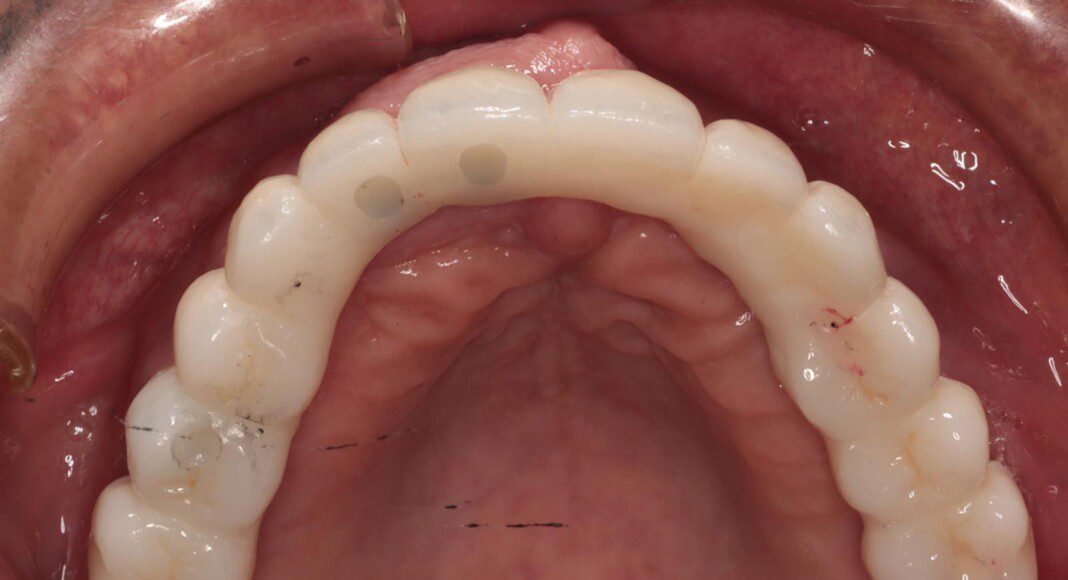

Zirconia bridge cemented to the titanium cylinders (tissue view) + one cemented unit on one old implant. The angle of this implant was too far forward. By cementing this one, we can still use it for retention and stability. Note the convex nature of the tissue interface for easy cleaning.